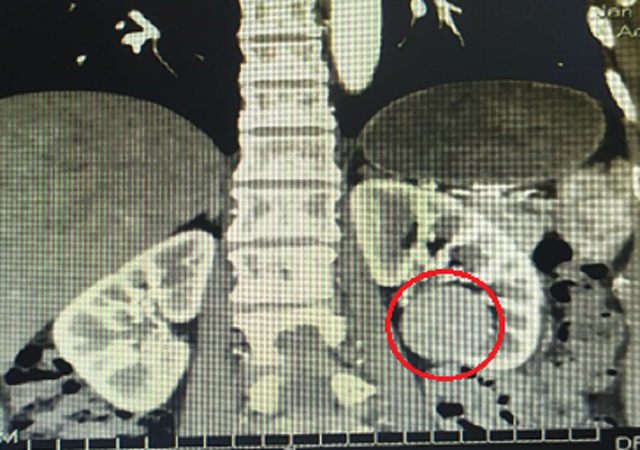

Qua chẩn đoán hình ảnh, bác sĩ phát hiện khối bướu lớn nằm ở vùng thận trái của người bệnh.

Trên hình ảnh siêu âm bác sĩ ghi nhận khối bướu ở thận trái nên chỉ định cho người bệnh thực hiện kiểm tra chuyên môn sâu. Hình chụp cắt lớp vi tính (CT-Scan) ghi nhận khối choán chỗ có kích thước 34x31mm sát dưới mặt trước rốn thận trái, có bờ đều rõ, không xâm lấn xung quanh.

Không nằm ngoài chẩn đoán ban đầu, kết quả giải phẫu bệnh sau mổ của bệnh nhân cho thấy, khối bướu là carcinoma (ung thư) tuyến thận. Bệnh nhân đang được theo dõi sát sau phẫu thuật, chưa ghi nhận bướu tái phát khi chụp cắt lớp vi tính.